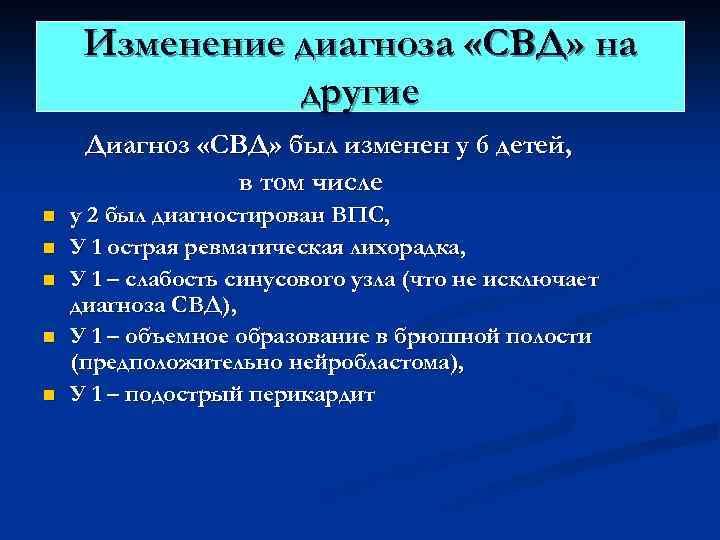

Изменение диагноза «СВД» на другие Диагноз «СВД» был изменен у 6 детей, в том числе n n n у 2 был диагностирован ВПС, У 1 острая ревматическая лихорадка, У 1 – слабость синусового узла (что не исключает диагноза СВД), У 1 – объемное образование в брюшной полости (предположительно нейробластома), У 1 – подострый перикардит